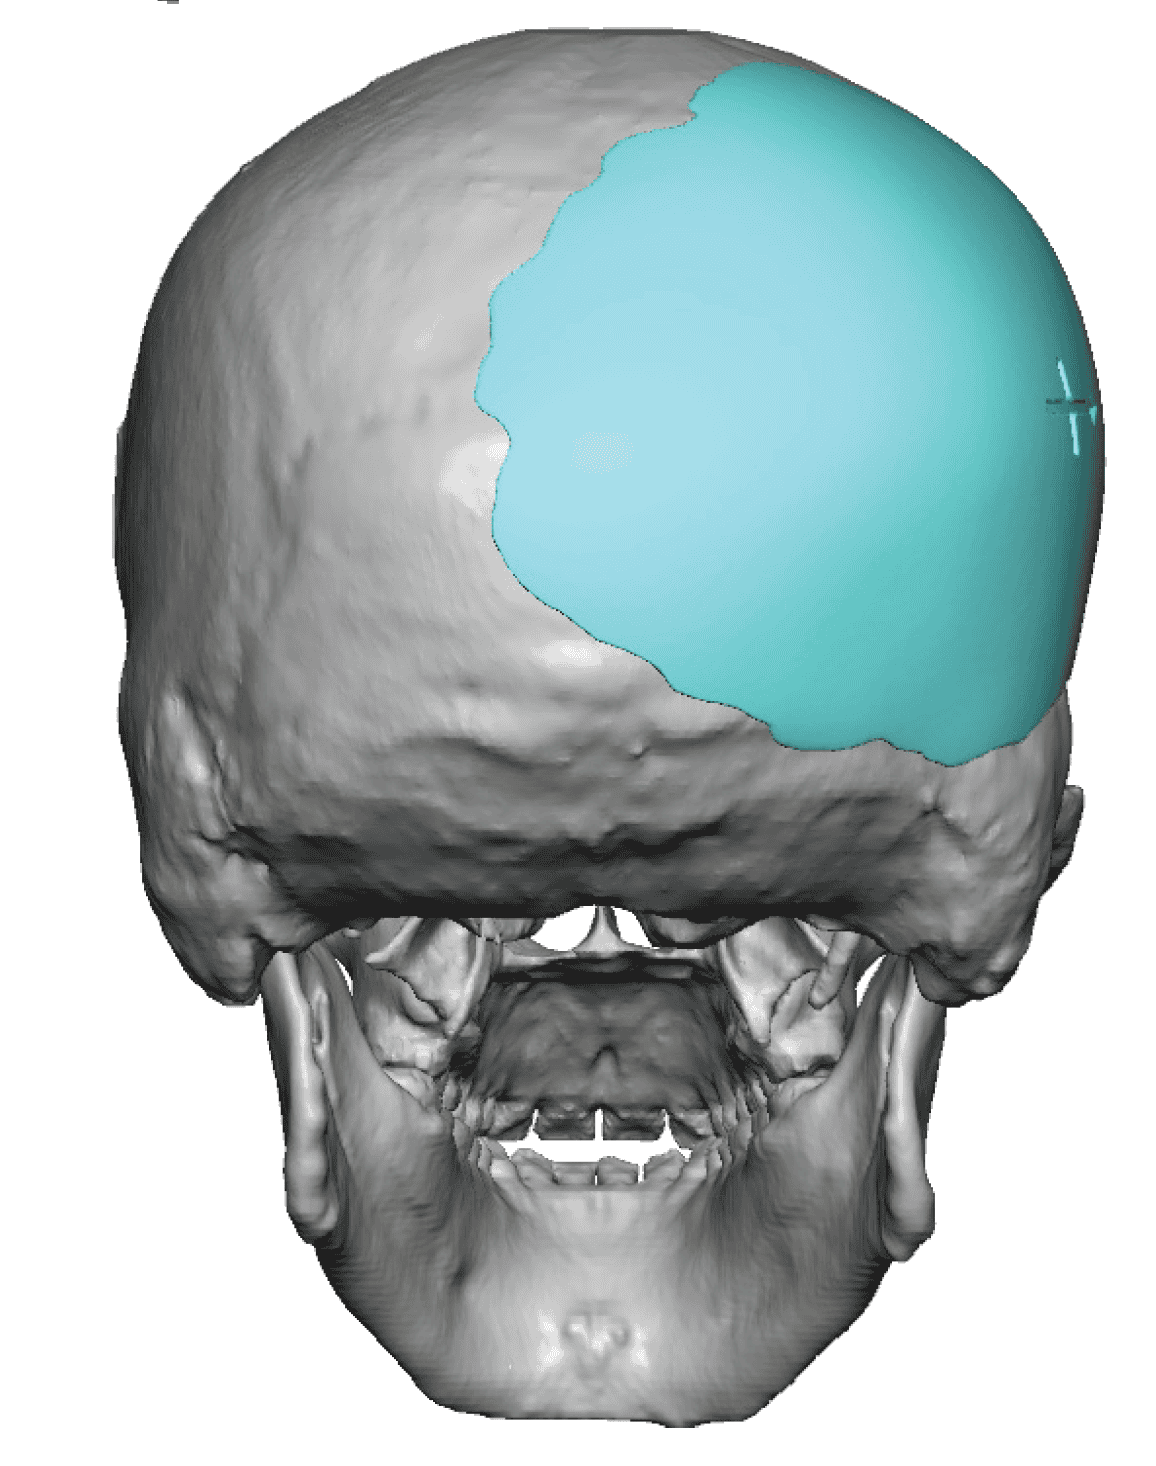

Severe narrowing skull deformity from prior sagittal craniosynostosis repair as an adult.

Complete replacement of entire skull by a custom implant with temporal fat injections.

Severe narrowing skull deformity from prior sagittal craniosynostosis repair as an adult.

Complete replacement of entire skull by a custom implant with temporal fat injections.